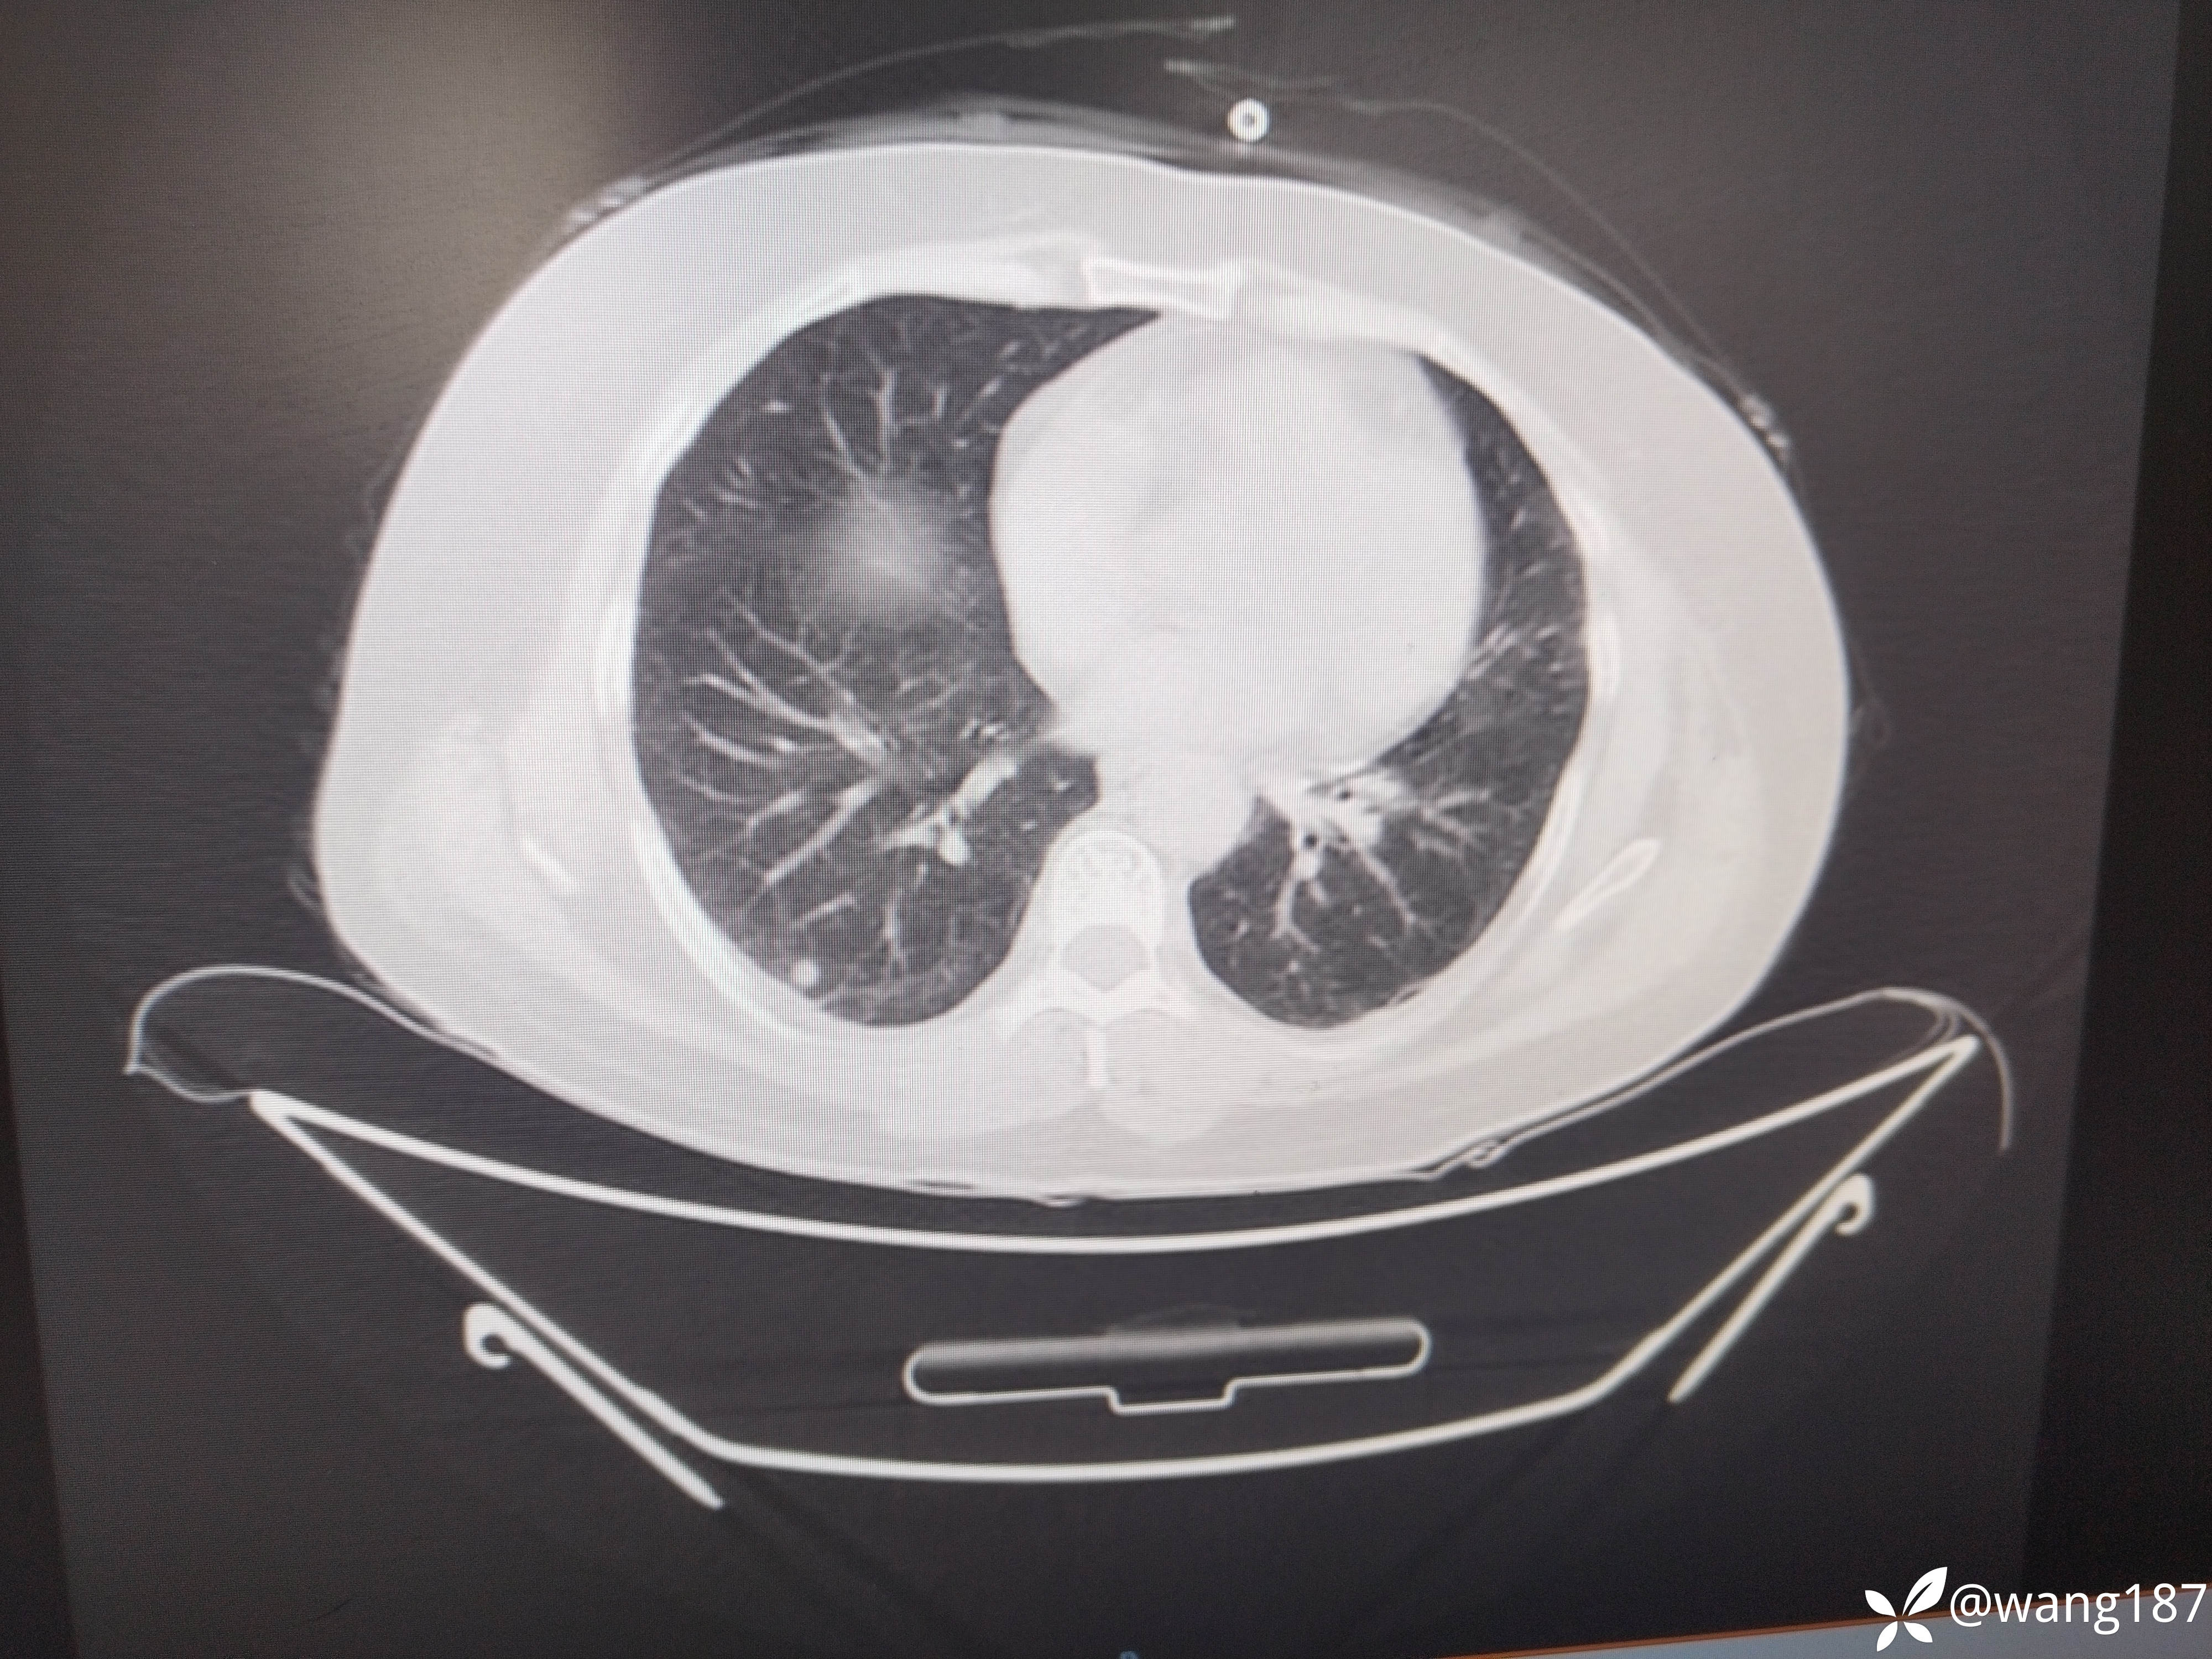

四肢肌无力伴有肌肌酸激酶升高。

患者女性,54岁,

主诉:四肢肌肉酸痛伴无力半个月,加重1天

现病史:半个月前无明显诱因出现双下肢肌肉酸痛,后出现双上肢肌肉酸痛,伴无力,伴活动受限,不能自行抬起、行走困难,伴肩背部疼痛,伴双眼睑、面部水肿,呈持续性,伴面部红斑,小便无泡沫,尿量无改变,无尿频、尿急、尿痛,无双下肢水肿,无恶心、呕吐,无心慌、胸闷,前往“当地医院”查心电图(2025-04-16):1、窦性心动过速2、T波异常 (可能是下壁心肌缺血)心肌酶谱(2025-04-16):血清肌酸激酶:8736U/L乳酸脱氢酶727U/L肌酸激酶同工酶52.18ng/mL心肌酶谱(2025-04-18)肌酸激酶:11605U/L乳酸脱氢酶620U/L;肝功(2025-04-18):丙氨酸氨基转移酶121U/L天门冬氨酸氨基转移酶429U/L谷氨酰氨基转移酶110U/L,尿常规:蛋白质+-尿潜血 2+;糖化血红蛋白(2025-04-18):8.1%;肩关节超声(2025-04-16)提示:1、肱二头肌长头腱腱鞘炎肌炎2、肩峰下-三角肌下滑囊炎,颈椎

上膜增厚。下肢肌电图未见异常,诊断为“横纹肌溶解”给予输液治疗(具体不详),症状无好转,1天前四肢肌肉酸痛伴无力症状加重,为求进一步诊治,遂来我院门诊以“1、皮肌炎2、2型糖尿病”为平诊收入我科,自发病以来,神志清,精神差,食欲差,睡眠差,大小便正常,近期体重未见明显增减。